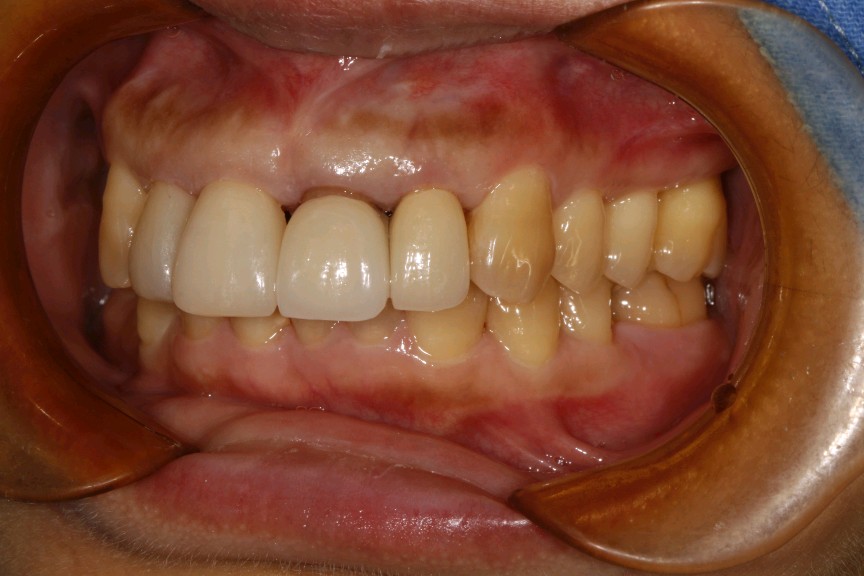

治疗计划:1、牙周治疗。2、21,22饵激光拆除牙冠。清理基牙,重新预备,西诺德全冠修复。3、11、12贴面修复。

这位患者就是错误的刷牙方式,加上牙周炎导致的牙龈萎缩,牙颈部暴露。最终只能拆除重新修复。既费钱又费时间。所以往往一些不起眼的小问题,生活中的一些不良小习惯,日积月累就会出现从小问题发展成大问题。使得前面的工作功亏一篑徒劳无功。一定要谨遵医嘱,使用正确刷牙方式,定期复查,及时发现及时杜绝。